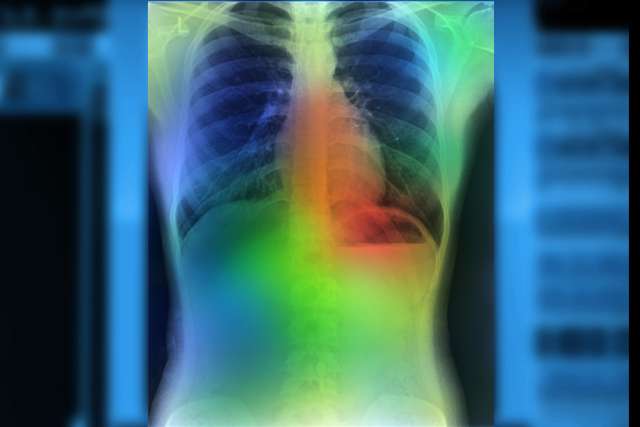

Radiation therapy

Radiation therapy uses high-energy X-rays to kill cancer cells or stop them from growing. We offer the most advanced methods of radiation. Your care team works with you to personalize every treatment plan and offer support.

UCLA Health specialists use precision medicine to tailor your treatment plan. We provide molecular testing (biomarker testing) to spot changes in the tumor’s DNA and understand its genetic makeup.

Using the results of biomarker testing, along with information about your overall health, family history and lifestyle, we identify the best treatment for you. The precision medicine approach guides us to the most effective lung cancer treatment plan.